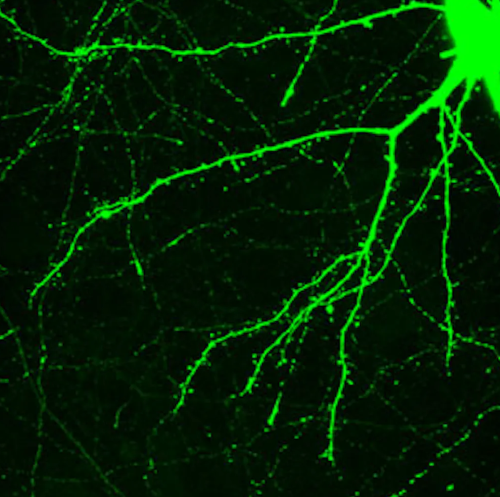

Research suggests that new skills, memories and attitudes are encoded in the brain by new connections between neurons – sort of like branches of trees growing toward each other. Neuroscientists even call the pattern of growth arborization.

Researchers using a technique called two-photon microscopy can observe this process in living cells by following the formation and regression of spines on the neurons. The spines are one half of the synapses that allow for communication between one neuron and another.

Scientists have thought that enduring spine formation could be established only with focused, repetitive mental energy. However, a lab at Yale recently documented rapid spine formation in the frontal cortex of mice after one dose of psilocybin. Researchers found that mice given the mushroom-derived drug had about a 10% increase in spine formation. These changes had occurred when examined one day after treatment and endured for over a month.